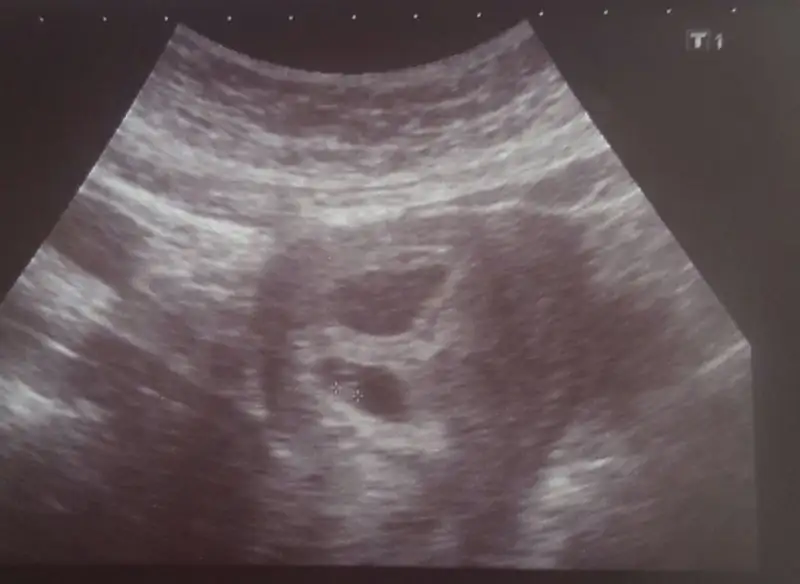

Bir tanesi ramziye göre erkek ama diğeri gözükmüyor.6+1 ikizlerimizin karından görüntüsü tahminlerinizi bekliyorum :)

Teşekkürler hayırlısı artık :)Bir tanesi ramziye göre erkek ama diğeri gözükmüyor.

Hangisi erkek üstteki mi altta ölçümü yapılan mi?

Cnm bu da diğer bebeğin olcumunun yapıldığı görüntü .Altta olcumu yapilan